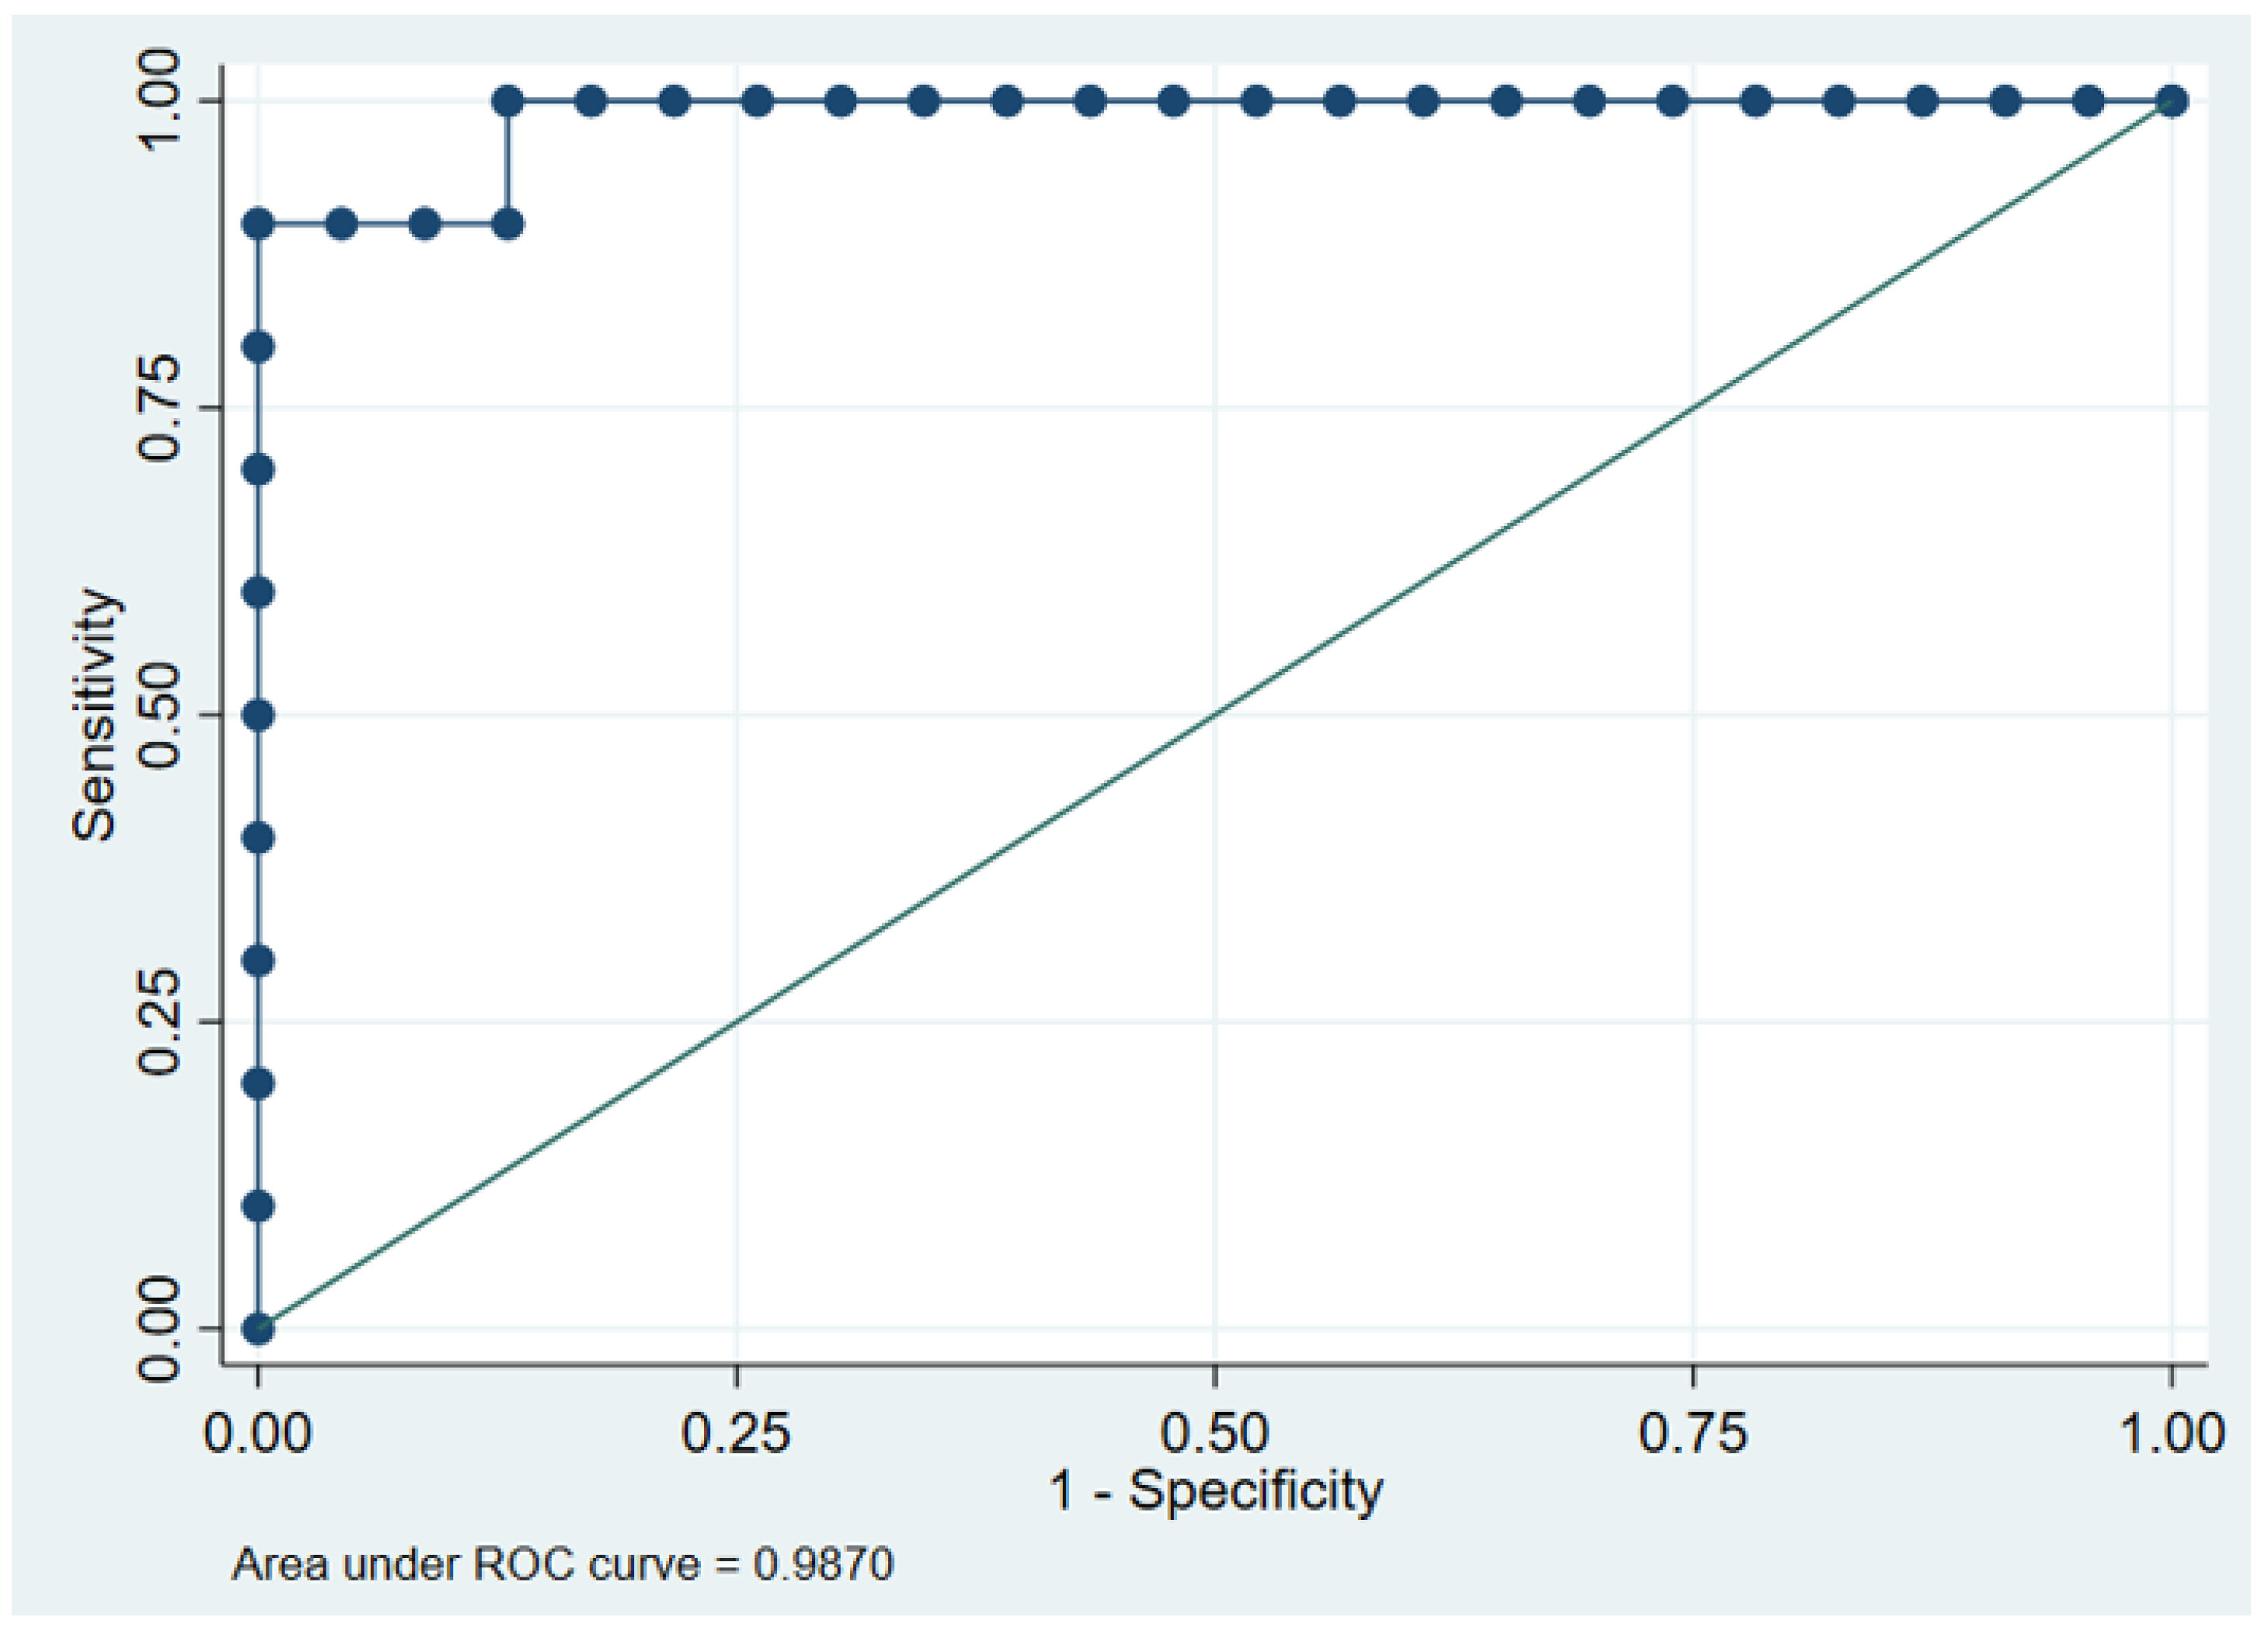

3.5. ROC Curve Analysis of FVF for Diagnosing Fatty Liver